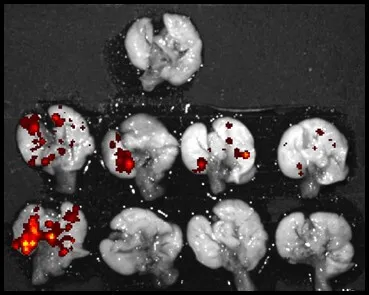

The Redox Biology and Pathology (RBP) Program studies the role of reactive oxygen species (ROS) in physiology and disease, develops therapies targeting redox pathways, and creates tools for redox research. While traditionally seen as damaging, ROS are crucial for normal cell function and the progres